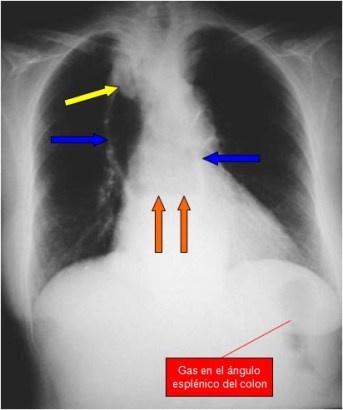

SIGNO DEL GRANO DE CAFÉ

Signo de obstrucción intestinal con estrangulación (vólvulo, hernia incarcerada,…), que provoca obstrucción simultánea a dos niveles -asa cerrada-. El asa afecta, llena de aire y doblada sobre sí misma, adquiere el aspecto de un grano de café con una banda central densa que corresponde a las paredes opuestas del asa estrangulada. Cuando la radiografía es en bipedestación puede aparecer un nivel hidroaéreo en cada segmento del intestino dilatado.

La fotografía corresponde a un paciente con vólvulo de sigma. Suele ser habitual en pacientes con vólvulo de sigma que el grano de café ocupe casi todo el abdomen. Hasta un 80 % de estos vólvulos se diagnostican solo con la radiografía de abdomen en decúbito. La ausencia de gas rectal contribuye a reforzar el diagnóstico.

El signo también ha sido descrito en obstrucciones en asa cerrada de intestino delgado, pero lo más habitual es que se aplique al vólvulo de sigma.

El Signo del grano de café también se ha llamado Signo de la U invertida y Signo del tubo doblado

SIGNO DE LA LÍNEA BLANCA

En la imagen del signo anterior también es visible el Signo de la línea blanca, formada por las paredes del sigma dilatado próximas entre sí, es decir, corresponde a la línea que divide en dos el «grano de café».

SIGNO DE LAS LÍNEAS CONVERGENTES

Es un signo de vólvulo de sigma que se ve al tiempo que el Signo del grano de café, pero no referido al luminograma del sigma dilatado sino a las paredes sigmoideas. Se trata de tres líneas que delimitan la pared del sigma (flechas), dos laterales y una central, más gruesa, formada por la aposición de las paredes de las dos partes del sigma, la que asciende y la que desciende. Las tres líneas convergen en la pelvis en la zona de la volvulación.

Este signo se ha denominado también Signo de Frimann-Dahl.